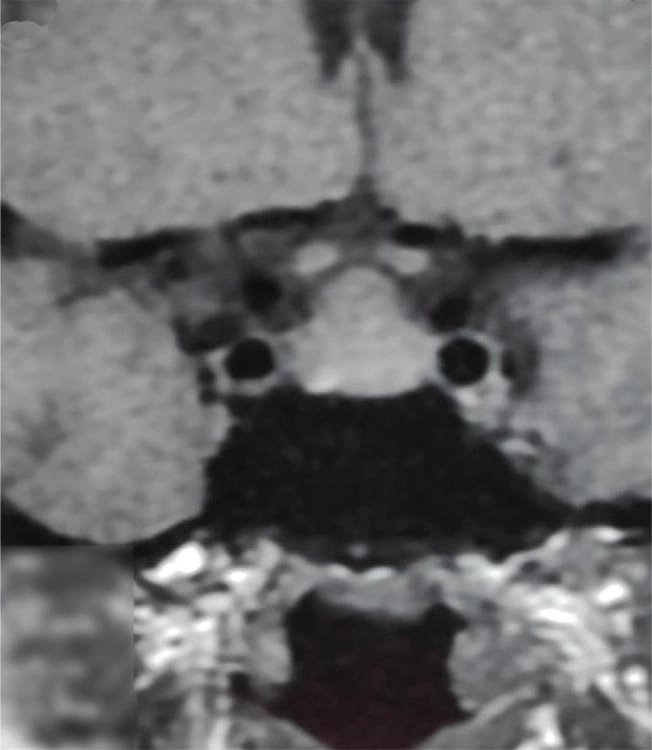

MRI-তে এই হাইপারপ্লাসিয়া সাধারণত গম্বুজ-আকৃতির ও সমমিত হয় এবং হোমোজেনাস সিগনাল ইন্টেনসিটি দেখায়, যেখানে সাধারণ নন-ফাংশনাল পিটুইটারি অ্যাডেনোমা নানা আকার ও অসমতা নিয়ে দেখা যায়।

তাঁর দাবি, MRI-তে ‘DOME Sign’ থাকা এবং TSH বাড়তি থাকলে, সেটি হাইপোথাইরয়েডিজম-জনিত হাইপারপ্লাসিয়ার সম্ভাবনার কথা নির্দেশ করে এবং এই রোগীদের শুধুমাত্র লেভোথাইরক্সিন দিয়ে চিকিৎসা করলে পূর্ণ আরোগ্য সম্ভব।